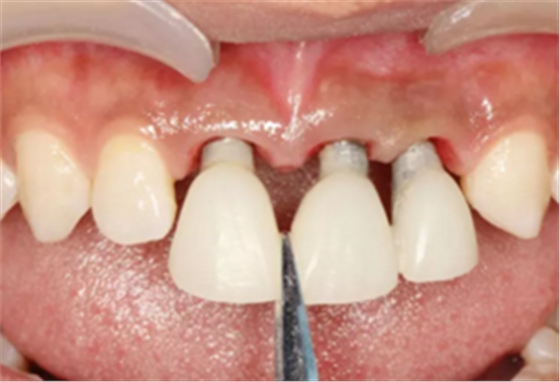

(2)即刻种植、即刻临时修复。术中不翻瓣微创拔除牙根,牙槽 窝骨壁完整。在多级导板辅助下完成种植窝洞制备,植入Bego柱形种植 体,型号分别为:上颌右侧中切牙位点4.1mm×15mm、上颌左侧中切牙 位点?3.75mm×15mm、上颌左侧侧切牙位点3.25mm×15mm,扭矩均为 35N·cm。种植体与唇侧骨壁间隙约2mm,植入Bio-Oss®Collagen骨胶 原。戴入桥用钛临时基台,临时冠就位顺利,自凝树脂口内粘接后适当修整 外形,充分磨光,调 至正中 、前伸 和侧方 与对颌牙均无接触。术后 根尖片显示种植体位置、方向良好。

图11 戴入临时修复体

图12 即刻修复完成